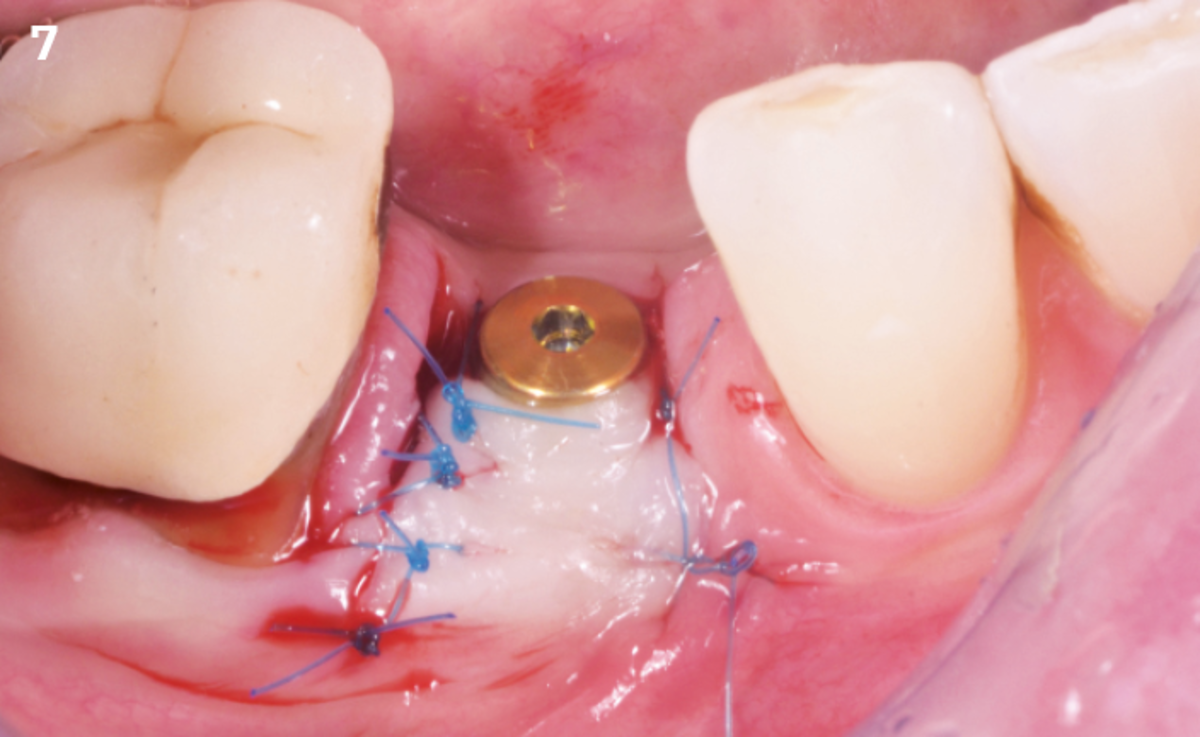

Extraction socket management with REGENFAST®

Ridge reconstruction before implant placement

"After the extraction, I realized that the buccal wall was missing and I had to leave the membrane exposed. The regenerative potential of the site could be poor, so I decided to boost the biomaterials’ effect with polynucleotides and hyaluronic acid."

The patient (45 years old, female, non-smoker, no previous pathologies) is referred for extraction of tooth 45 and immediate implant placement. The site showed an increased probing depth and a marked bone loss.